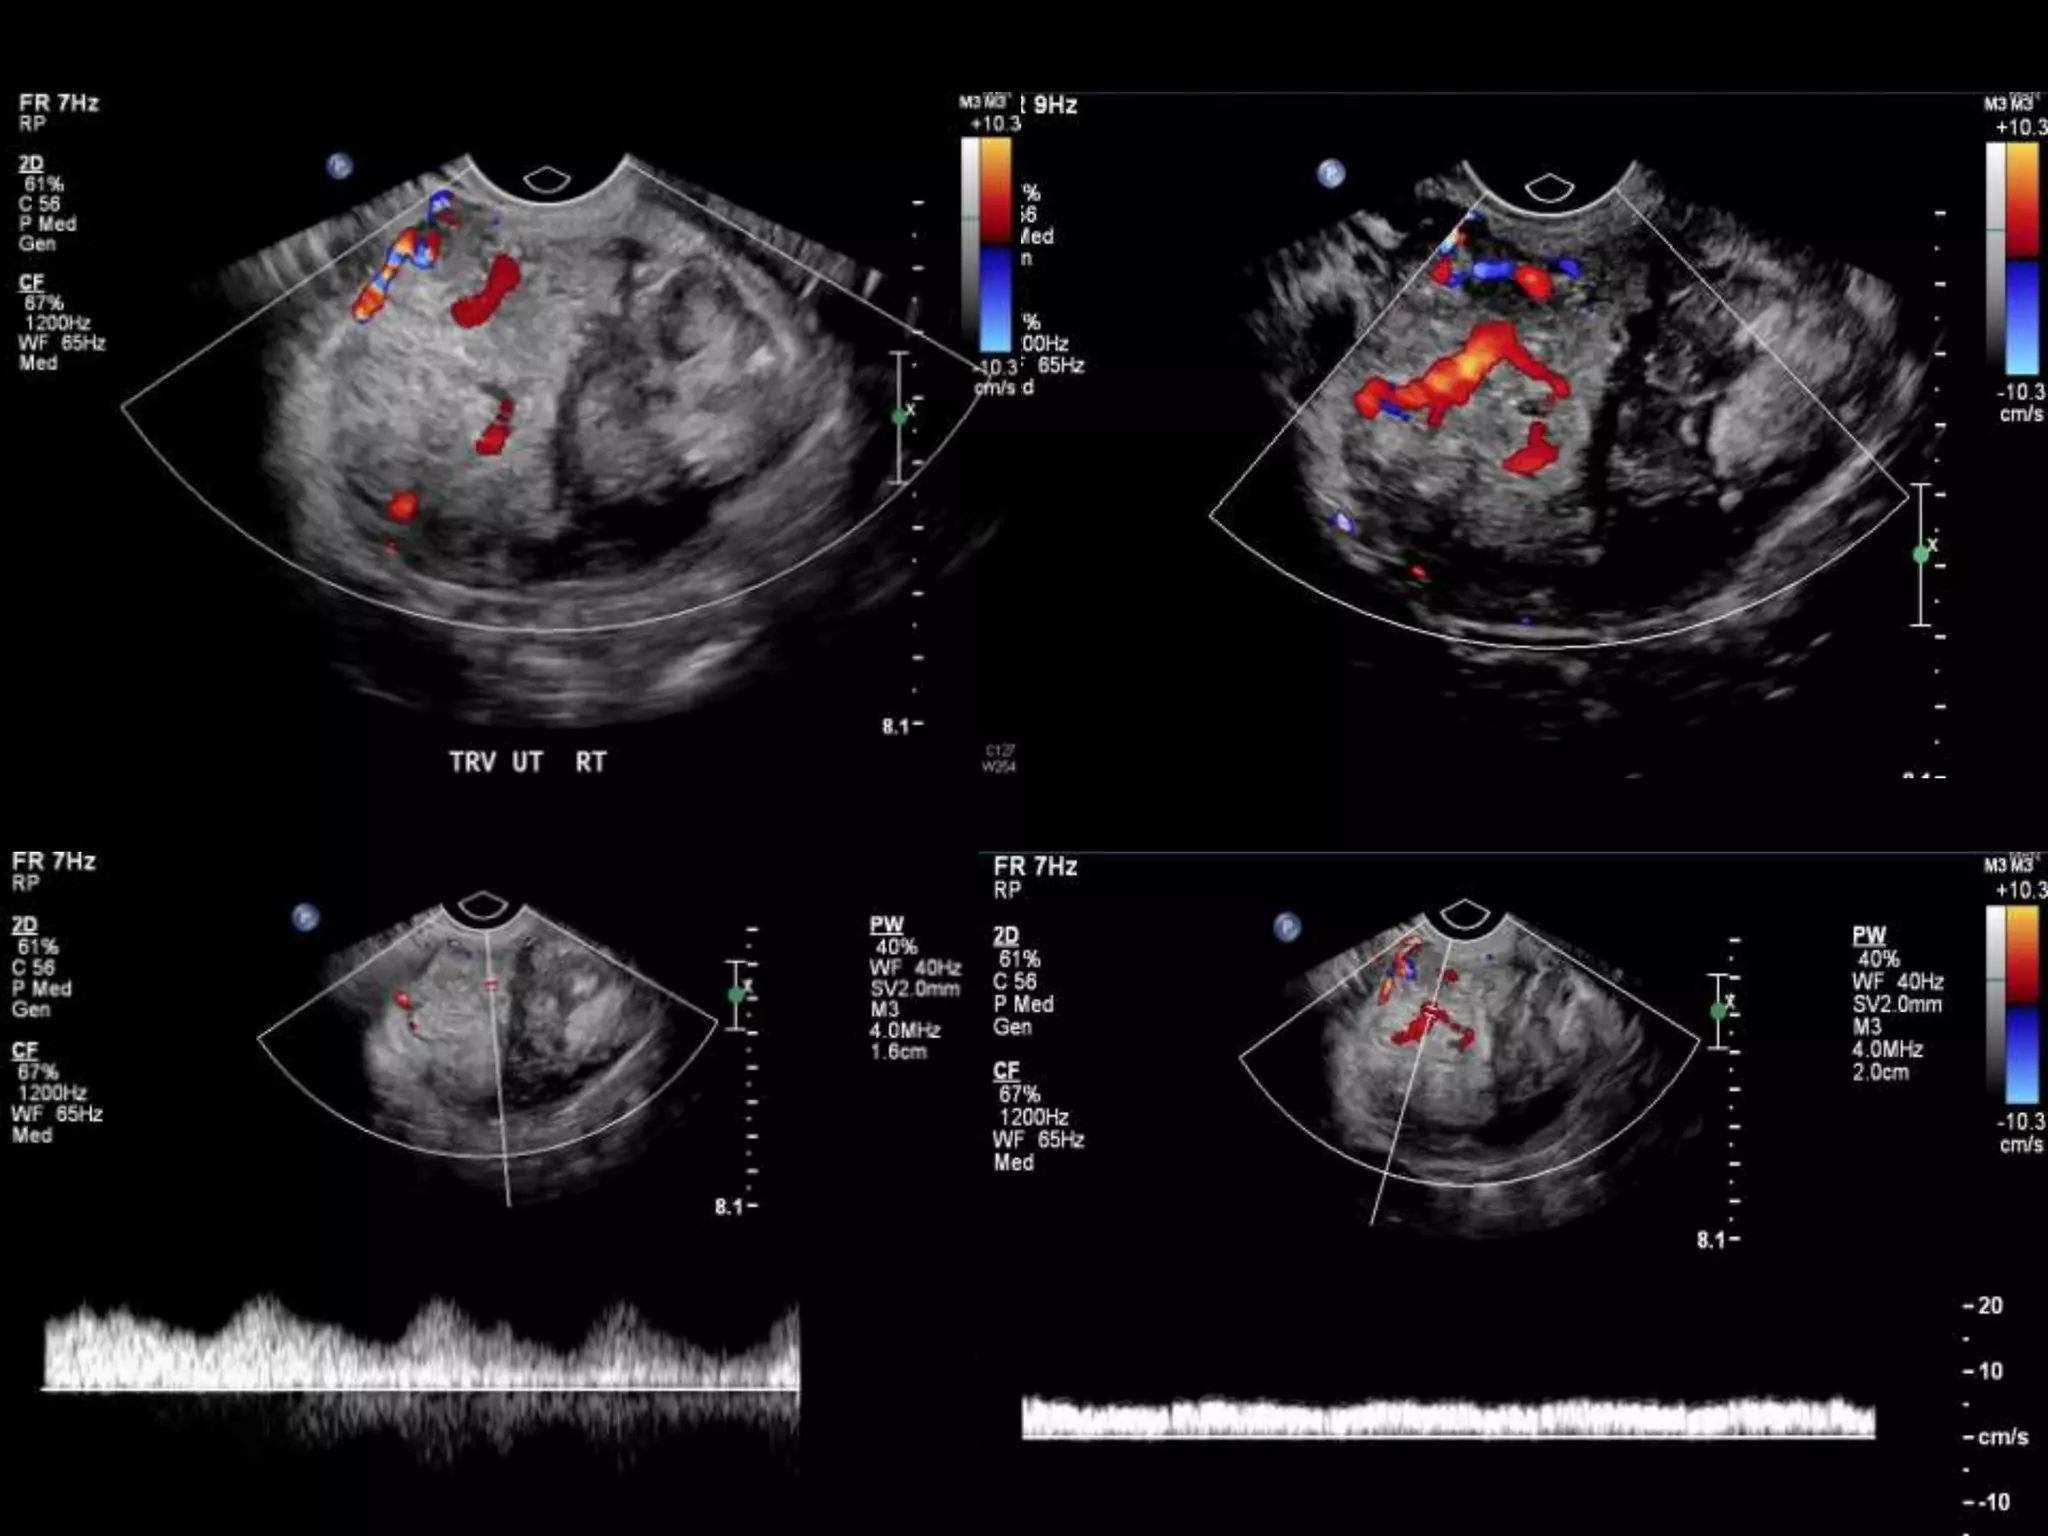

โ€ข 40 yo female 8.5 weeks pregant

โ€ข S/P D&C for pregnancy implanted at site of

c-section scar

โ€ข 6 weeks post D&C patient presents with

heavy persistent bleeding

โ€ข For Pelvic US

โ€ข HCG = 451 mIU/mL

D&C complicated by Perforation,

AVM w RPOC at Site of Perforation

โ€ข AVM โ€“ Acquired or Congenital

โ€ข Acquired

โ€“ Traumatic โ€“ D&C, TAB, uterine surgery

โ€“ Less common: Endometrial / Cervical CA, GTD

โ€“ Clue on US: numerous tortuous vessels, high velocities

โ€ข Tx:

โ€“ transcatheter arterial embolization

โ€ข Potential to preserve fertility

โ€“ UA ligation, hysterectomy

Angio after MRI

POST PROCEDURE

S/P embolization of right UA and left UA due to

cross collateralization

1 month follow up

HCG < 5 mIU/mL

No flow in area โ€“ smaller in size

Felt residual hematoma

Will continue US follow up